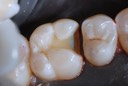

Photos of Clinical Operations

Drs. Peter Kearney, Terry McKay, John St. Germain, and Laurie Vanzella - Mentors